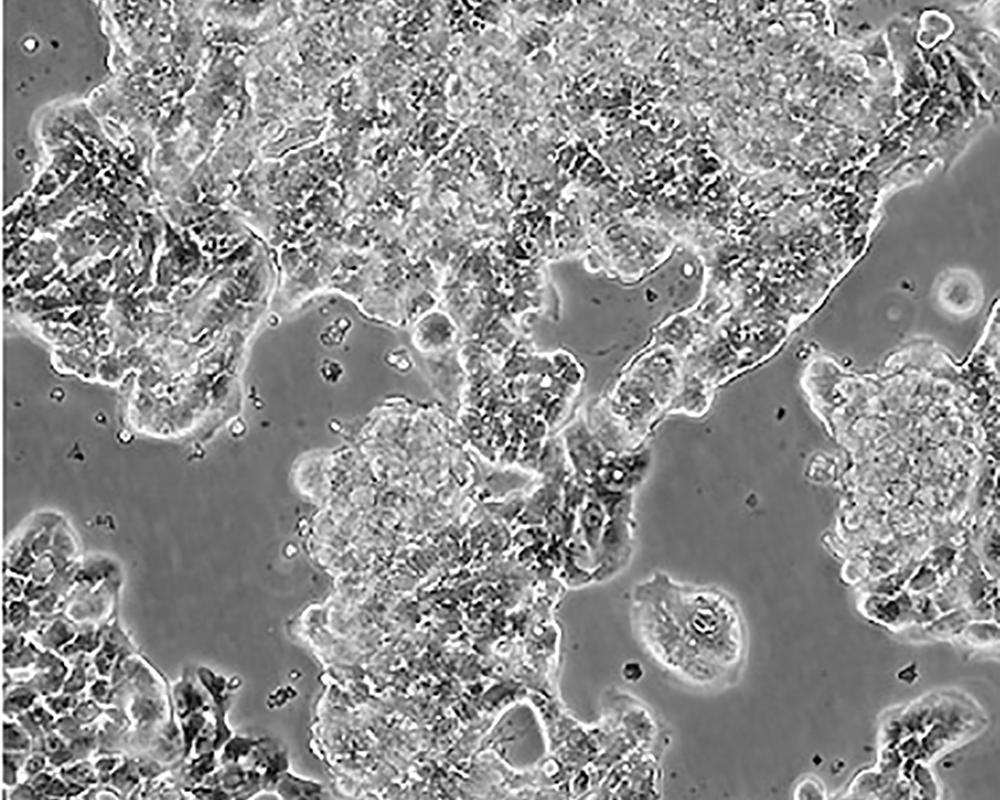

ZR-75-1 [ZR751]

產(chǎn)品名稱 ZR-75-1 [ZR751]

中文名稱 人乳腺癌細胞

組織來源 浸潤性導(dǎo)管癌;腹水轉(zhuǎn)移;女性

生長特性 adherent

形態(tài)特征 epithelial

細胞描述 該細胞產(chǎn)生高水平的黏液素MUC-1 mRNA,低水平的MUC-2 mRNA,但不表達MUC-3基因;表達雌激素受體。